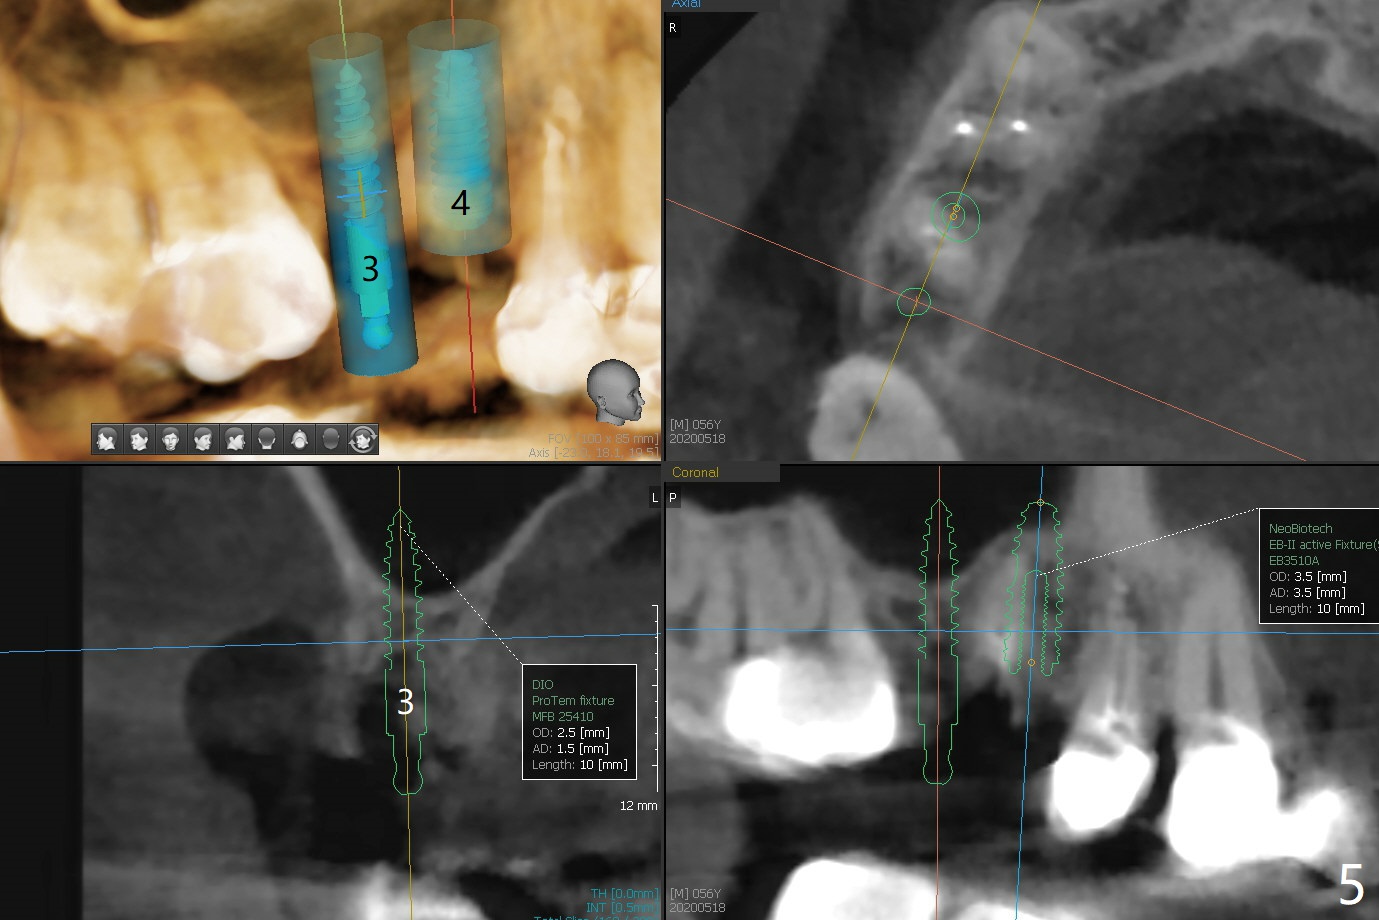

A 56-year-old man complains of food impaction under UR FPD (fixed partial denture, bridge). Floss goes through between #4 abutment and retainer (Fig.1 red arrow and *). After sectioning the FPD as indicated by black dashed line in Fig.2,3, try to initiate osteotomy at #3 with 1.2 and 1.5 mm drills for 5 mm (bone height) and 1.0 and 1.5 mm Tatum micro-osteotomes for sinus lift and place a 2x8.5 mm IS mini-implant. If it is feasible, place a 4x14 mm tissue-level implant slightly mesial at #4 (Fig.5). If not, place a larger one (5.0 mm) slightly distal for a cantilever FPD (Fig.4).